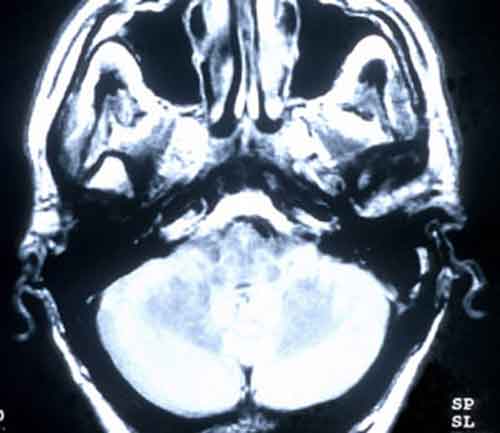

Le malattie psicogene, in passato conosciute come patologie isteriche, possono portare a sintomi molto gravi come crampi dolorosi e paralisi, senza apparenti cause fisiche.brain_scan Un nuovo studio dell’Universita’ di Cambridge ha scoperto pero’ che il cervello degli individui che soffrono di malattie psicogene funziona diversamente. I disturbi psicogene possono sembrare molto simili alle malattie causate da danni ai nervi, al cervello o ai muscoli o alle malattie genetiche del sistema nervoso. Tuttavia, a differenza delle organiche, le patologie psicogene apparentemente non hanno alcuna causa fisica, cosa che le rende difficili da diagnosticare e ancor di piu’ da trattare. “I processi che portano a questi disturbi sono poco compresi, complessi e altamente variabili.

Ne consegue che anche i trattamenti risultano difficili, spesso lunghi e in molti casi con scarsi margini di recupero. Per migliorare le terapie e’ quindi importante comprendere il meccanismo di base che si cela dietro lo sviluppo di una malattia psicogena”, ha detto James Rowe, autore della ricerca pubblicata sulla rivista Brain. Lo studio ha coinvolto pazienti con distonia psicogena e pazienti con distonia organica per comprendere come mai diverse patologie riescano a causare lo stesso disturbo. Entrambi i tipi di distonia provocano contrazioni muscolari dolorose e invalidanti che colpiscono la gamba. I pazienti ammalati della variante organica posseggono una mutazione del gene DYT1 che causa il sintomo. I pazienti psicogeni sembrano non possedere alcuna spiegazione fisica alla malattia. Attraverso le scansioni cerebrali, il team di ricercatori ha pero’ scoperto che il flusso sanguigno e l’attivita’ cerebrale dei pazienti psicogeni in relazione al movimento e al riposo della gamba risultano alterati rispetto al flusso e alle attivita’ delle persone sane e delle persone con malattia organica.